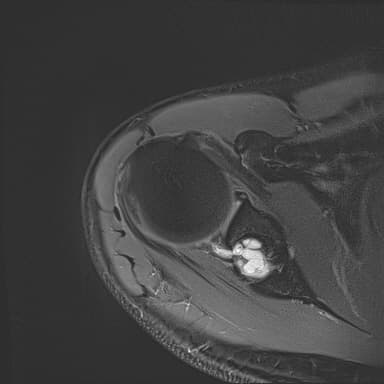

어깨 mri 좀 봐주세요 물혹있다고 하는데 수술해야 하나요?

하도 안 나아서 우측 견관절도 mri 촬영을 했는데 물혹이 있네요